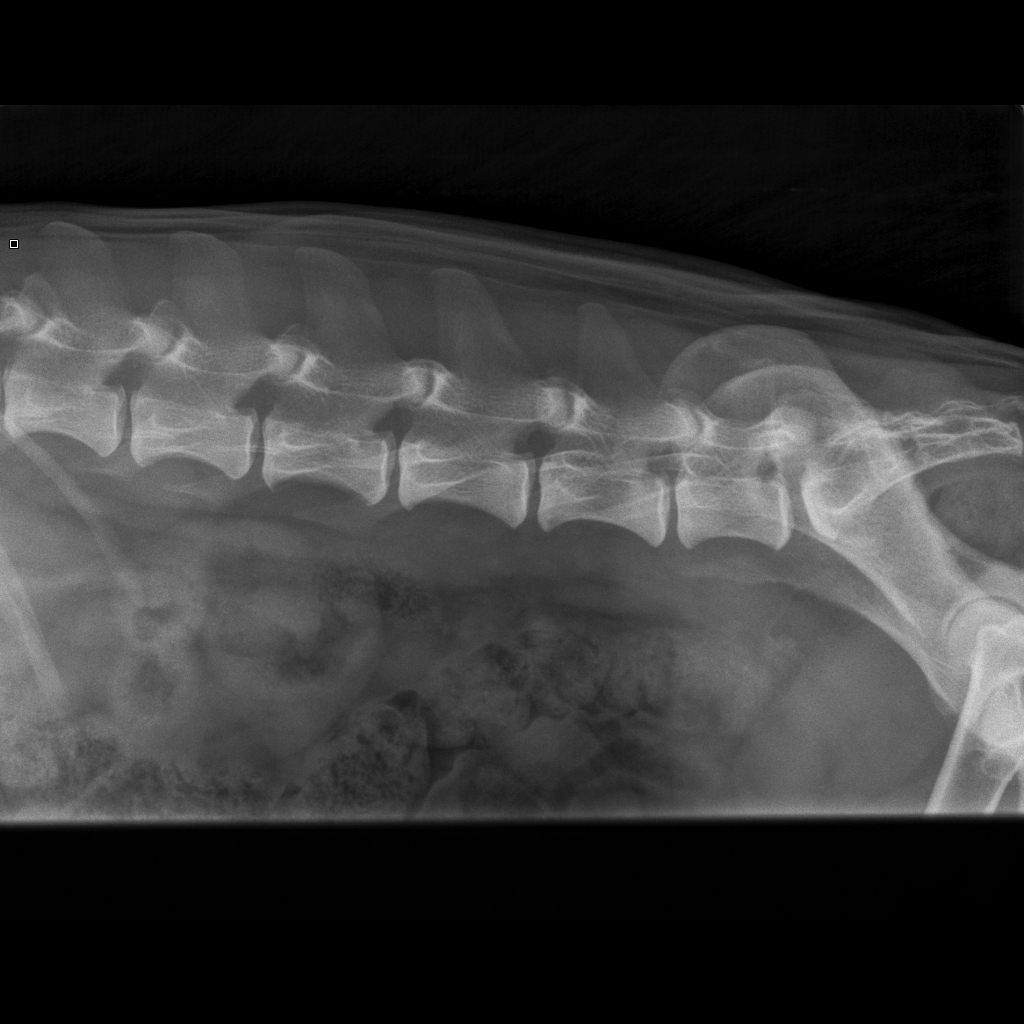

Qisa viety eläinlääkäriin 19.7.13, koska se kiljahtaa syliin nostettaessa (ei kiljahda, jos hyppä itse).

Lisäksi toisten koirien kanssa leikkiessä suuttuu, mikäli sen takapäähän osutaan. Oireilu kestänyt keväästä saakka.

Eläinlääketieteen kandidaatti Elise Luttinen:"Ei selkeää ontumaa. Takajalkojen liikkeet hieman laiskat,

ei ojenna takajalkoja kunnolla. Palpoidessa reagoi lievästi rinta-lannerangan liitosalueen paineluun.

Oikeaa lonkkaa ulospäin taivutettaessa reagoi, murahtaa."

Diagnoosi:"Selässä runsaasti spondyloosimuutoksia. Lannenikamia 7 kpl. L6-L7 välissä kiinni kasvanut

spondyloosisilloittuma, näkee sekä ventraalisesti että lateraalisesti. L3-L4, L4-L5 ja L5-L6 väleissä

kiinni kasvamassa olevat silloittumat. Jokaisessa lannenikamassa spondyloosimuutoksia. Myös rintarangan

alkuosassa nikamissa pieniä luupiikkejä. Varjon oireilu johtuu todennäköisesti spondyloosimuutoksista.

Liikunta ja harrastaminen Varjon voinnin mukaan."